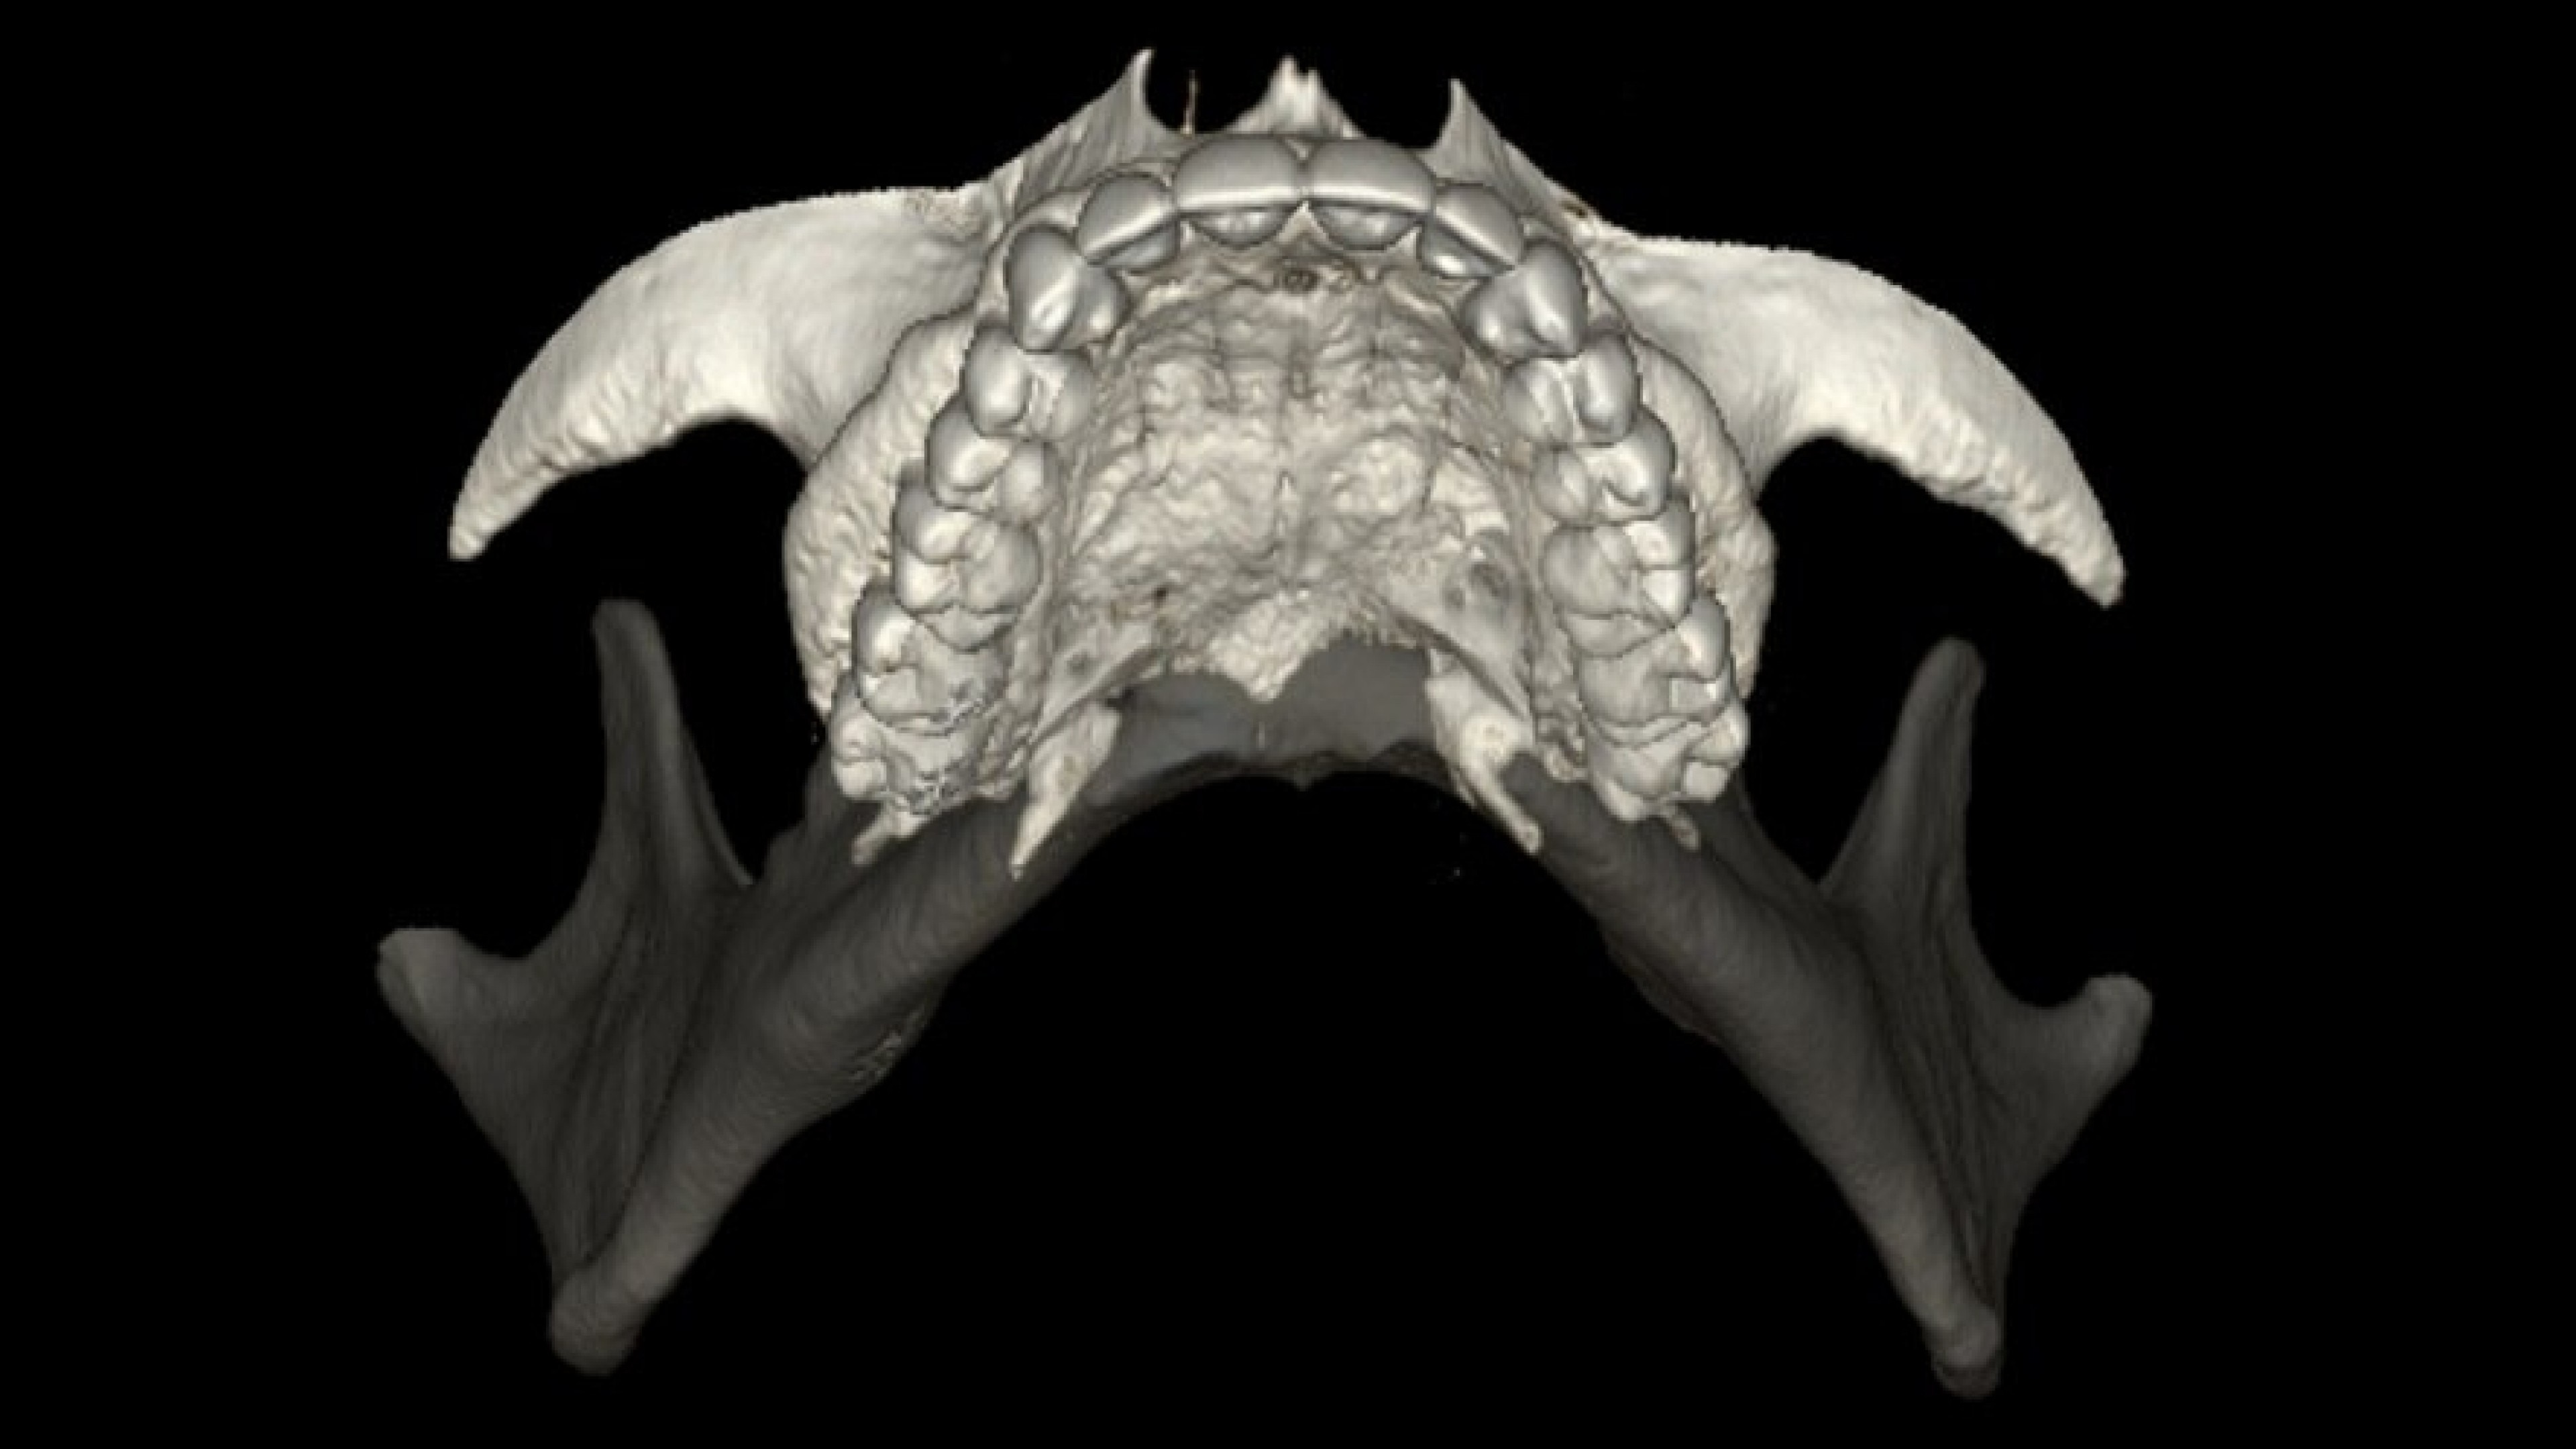

Panorex and oblique views

You can adjust or redraw curves used to generate views during the procedure

• The curve used to generate panorex and oblique views is drawn on selected axial views. It can be adjusted or redrawn easily at any time during Dentascan procedures.

• Axial panorex and oblique views remain cross referenced on the screen. Oblique views are generated in real time when the cursor is moved on axial or panorex views. A similar feature exists when the cursor is moved on a panorex or oblique view.